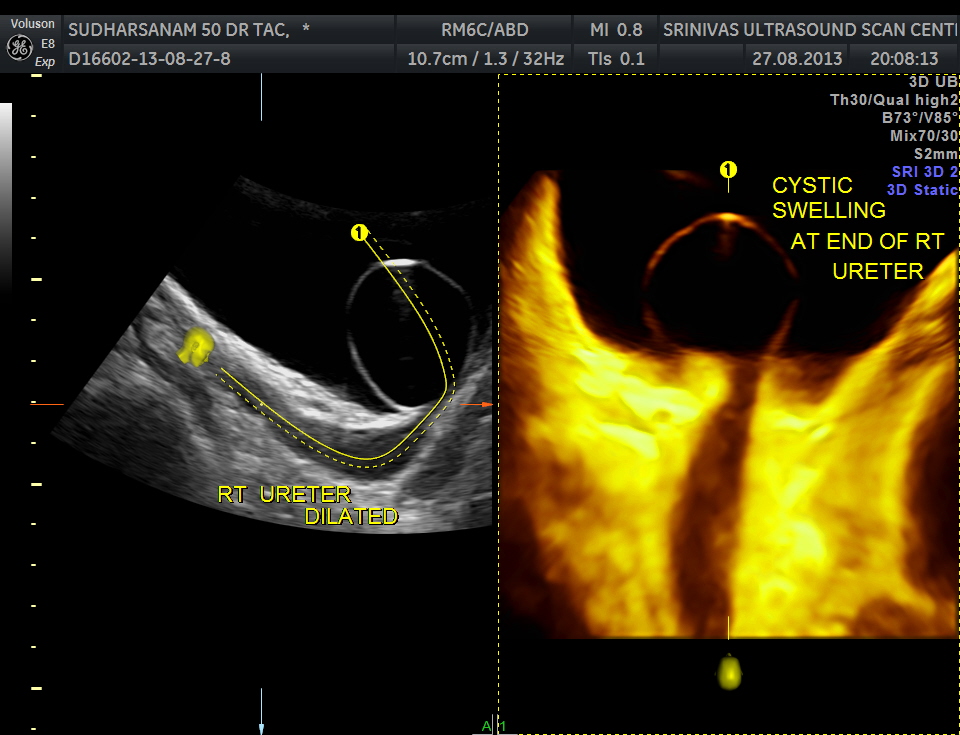

The urinary bladder showed the following :

given below are few other reconstructions

The patient was seen by the urologist and an IVP was done , which proved the diagnosis of orthotopic ureterocele . (a ureterocele entirely within the bladder.)

He has been advised cystoscopic surgical correction.